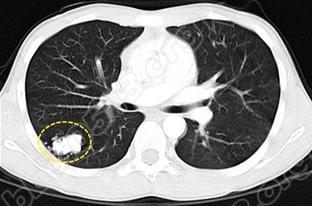

说到肺部结节,很多人不知道是怎么回事?而肺部又怎么会长结节呢?南通市第六人民医院解释,近些年来,体检出患有肺部结节的人数越来越多,而多数人没有明显症状,这是不是意味着没有事呢?下面就来听听专家的分析。

微创胸外科主任范岗指出:形成肺部结节的原因很复杂,并不是单一原因。虽然早期的肺部结节并没有太大症状表现,但数据显示肺部结节会恶化癌变。据调查,直径大于1厘米的肺内单发结节,恶性病变占到50%以上,直径大于2厘米的结节恶化率达到64%-82%,恶性概率随年龄增高而明显增高,因此对于体检发现的肺结节决不能忽视。